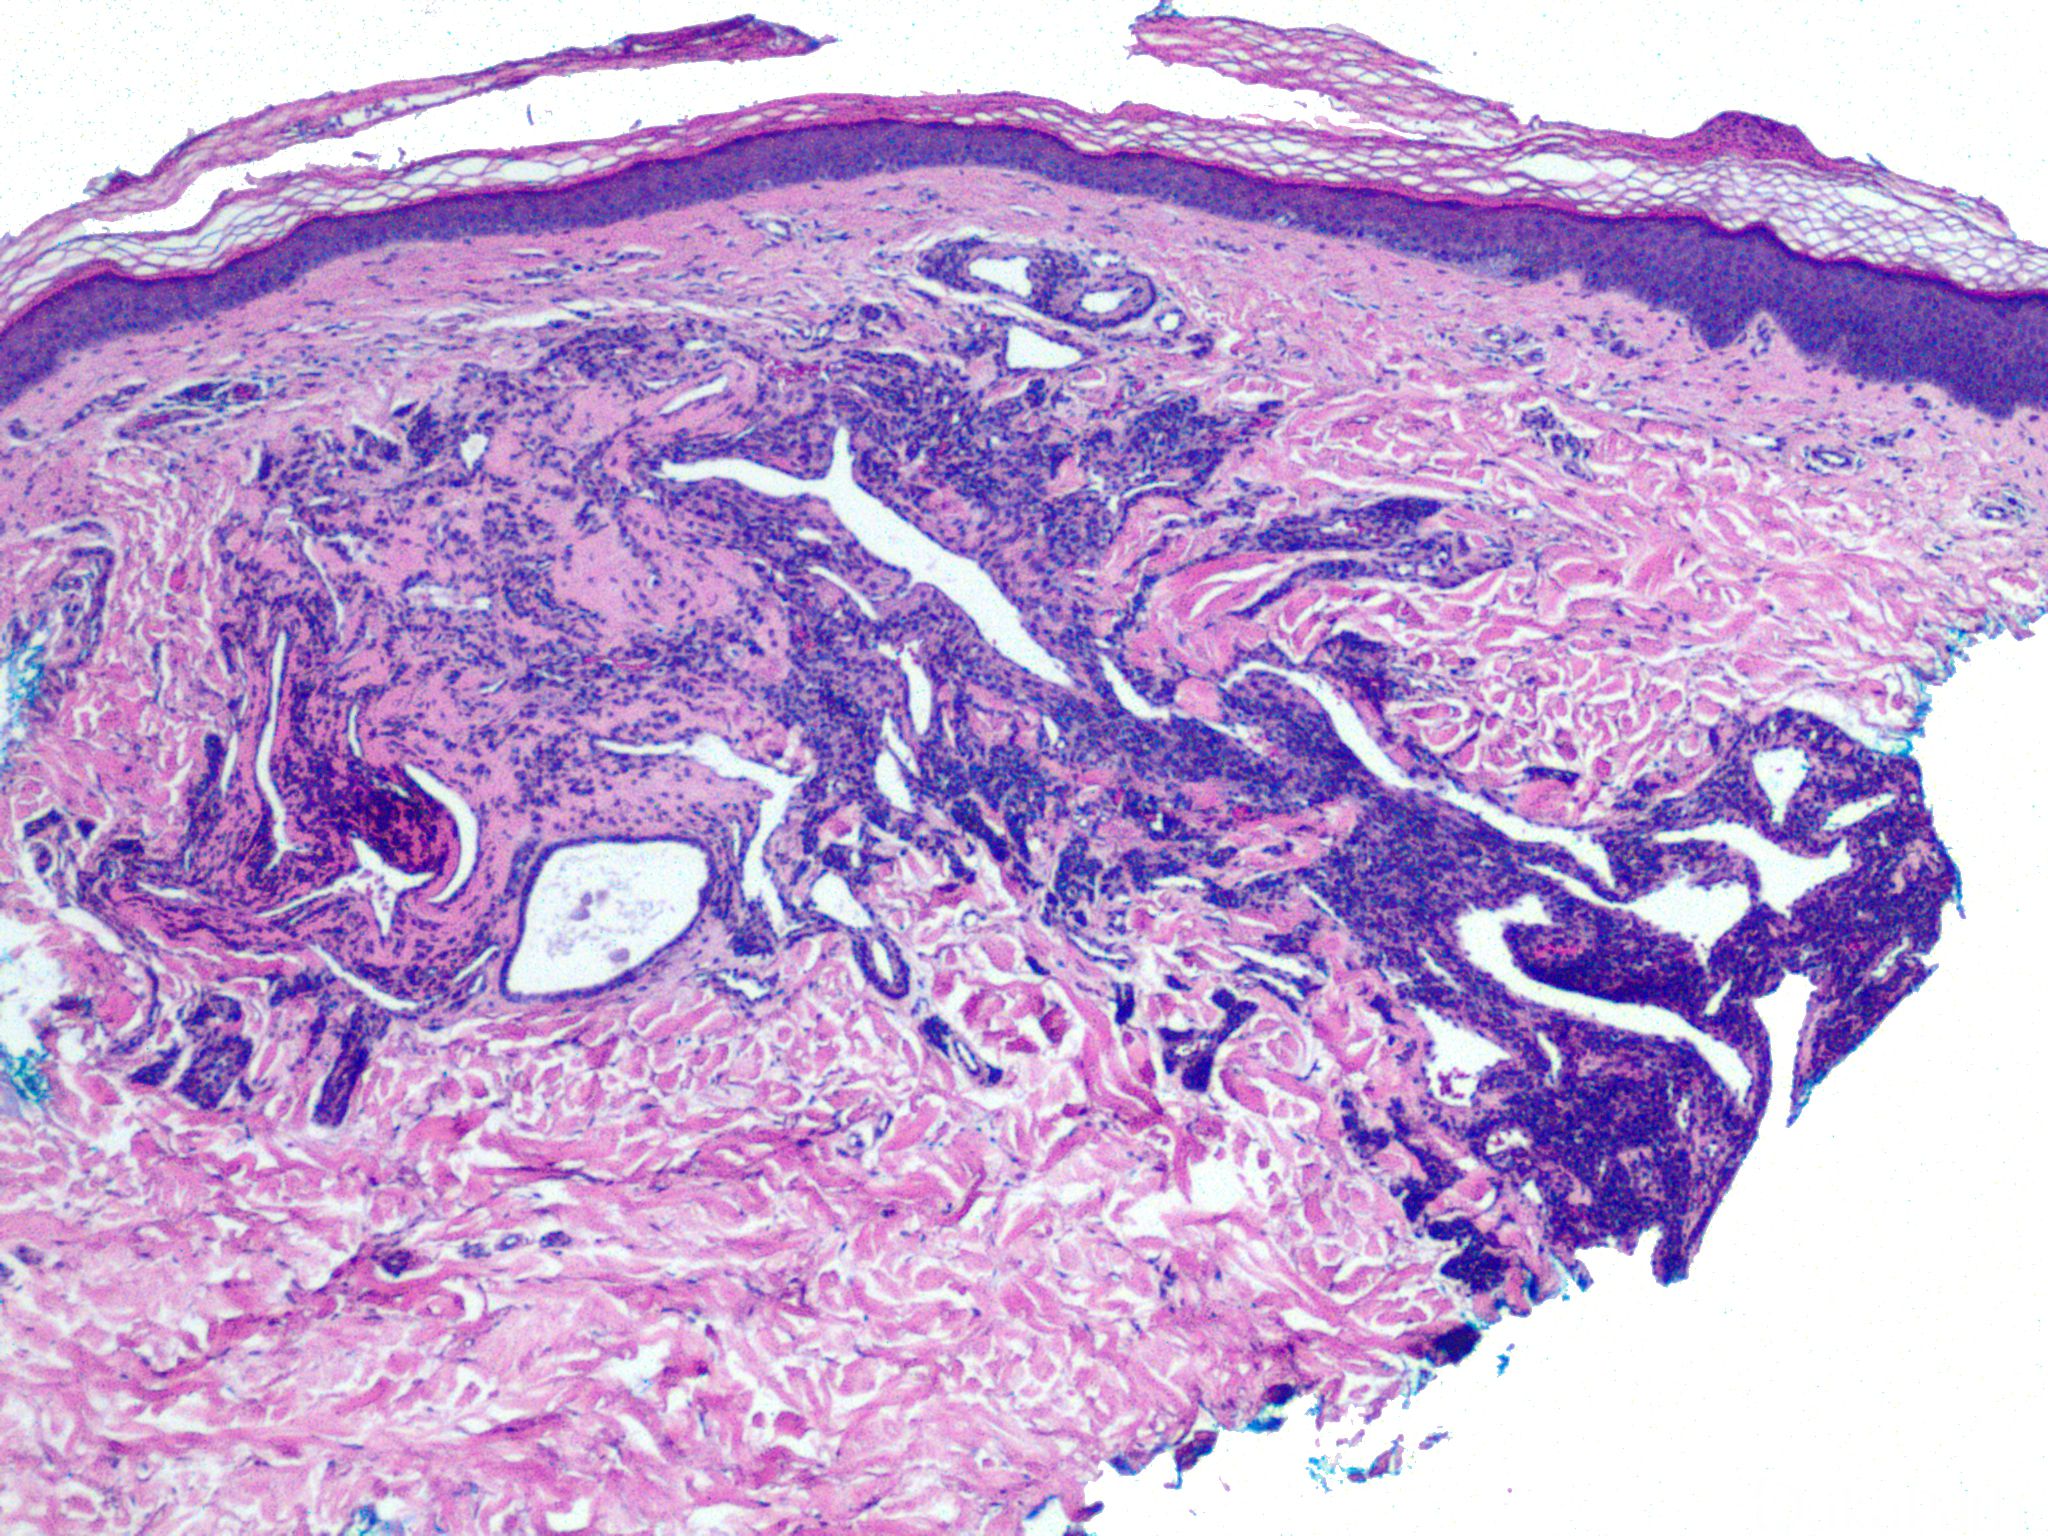

血管球瘤

glomus tumor